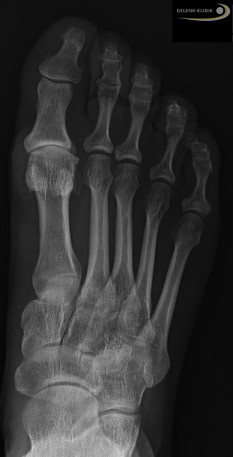

Gelenkerhaltende operative Therapien können nur bei einem leichten Hallux rigidus Grad 1 und 2 angewendet werden. Der Gelenkspalt muss im Röntgenbild noch deutlich sichtbar sein. Eine frühzeitige Indikationsstellung ist von entscheidender Bedeutung für den Erfolg dieser Operation.

Zur Beurteilung der Ausgangslage der Cheilektomie sind Röntgenaufnahmen in zwei Ebenen unter Belastung notwendig: insbesondere seitlich sowie in der Aufsicht von oben auf das Großzehengrundgelenk. Dadurch kann der Arzt den noch vorhandenen Gelenkspalt sicher beurteilen.

Üblicherweise ist die Indikation zu einer Cheilektomie gegeben, wenn sich die Knochenüberstände (Osteophyten) auf das obere Gelenkdrittel konzentrieren. Im seitlichen Röntgenbild sollte sich die vorhandene Knorpelschädigung vorwiegend auf obere Drittel der Gelenkrundung konzentrieren. In diesem Bereich des Gelenks ist auch die Wirkung der Keilentfernung auf die dorsale Beweglichkeit, also das Abknicken der Zehe nach oben, am größten.